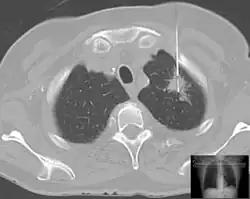

Es gibt verschiedene Formen der Gewebe- oder Probenentnahme. Meist werden Biopsien mit Spezialkanülen durchgeführt. Je nach dem verwendeten Instrument spricht man von:

Meist wird zunächst ein kleiner Hautschnitt gemacht, vor allem bei weitlumigen Biopsienadeln. Biopsien können, je nach Organ, ohne Sichtkontrolle („blind“) oder in Kombination mit bildgebenden Verfahren durchgeführt werden.